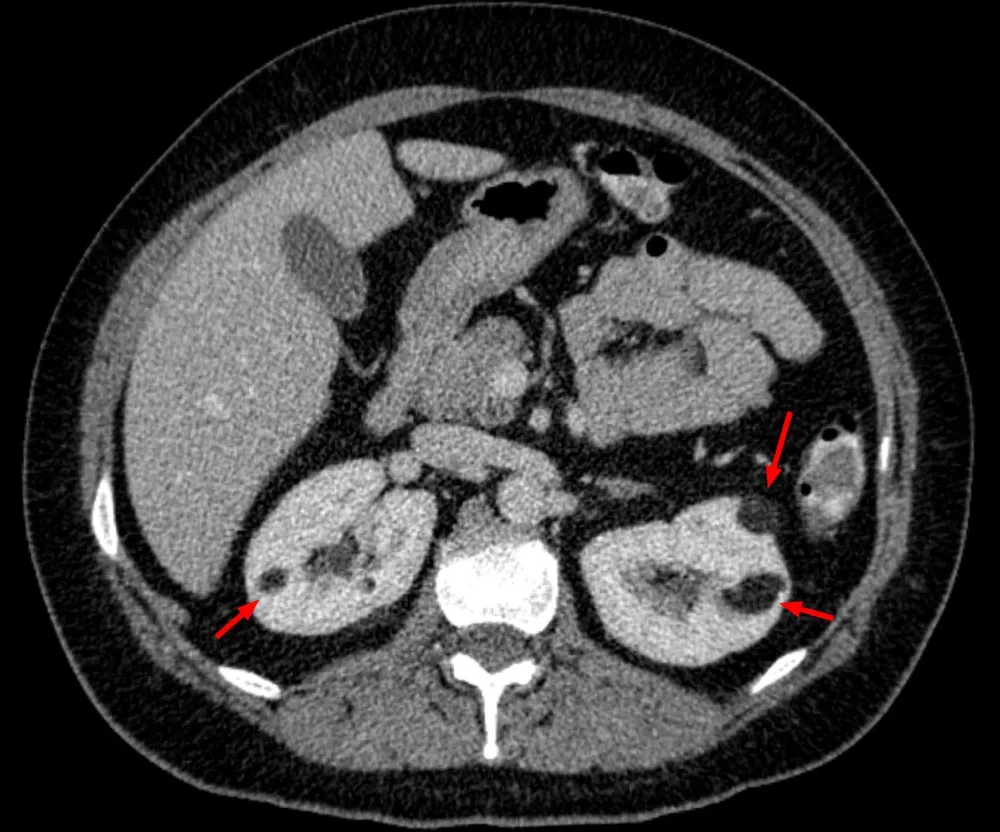

* Pacientes com **AML múltiplos (≥3), bilaterais e/ou grandes(ou seja, ≥4 cm)** têm maior probabilidade de ter CET (imagem abaixo).

* Nestes pacientes é essencial realizamos uma avaliação completa para CET, que inclui avaliação clínica, critérios diagnósticos e até testes genéticos).

TC abdome sem contraste evidenciando imagens hipodensas na região cortical de ambos os rins